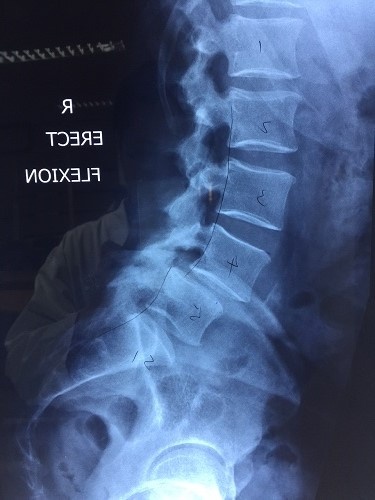

Phẫu thuật cột sống cho bệnh nhân nước ngoài

BV Hữu Nghị Việt Đức (Hà Nội) vừa nắn trượt cột sống cho một bệnh nhân quốc tịch Anh thành công với sự hỗ trợ định vị chính xác của robot.